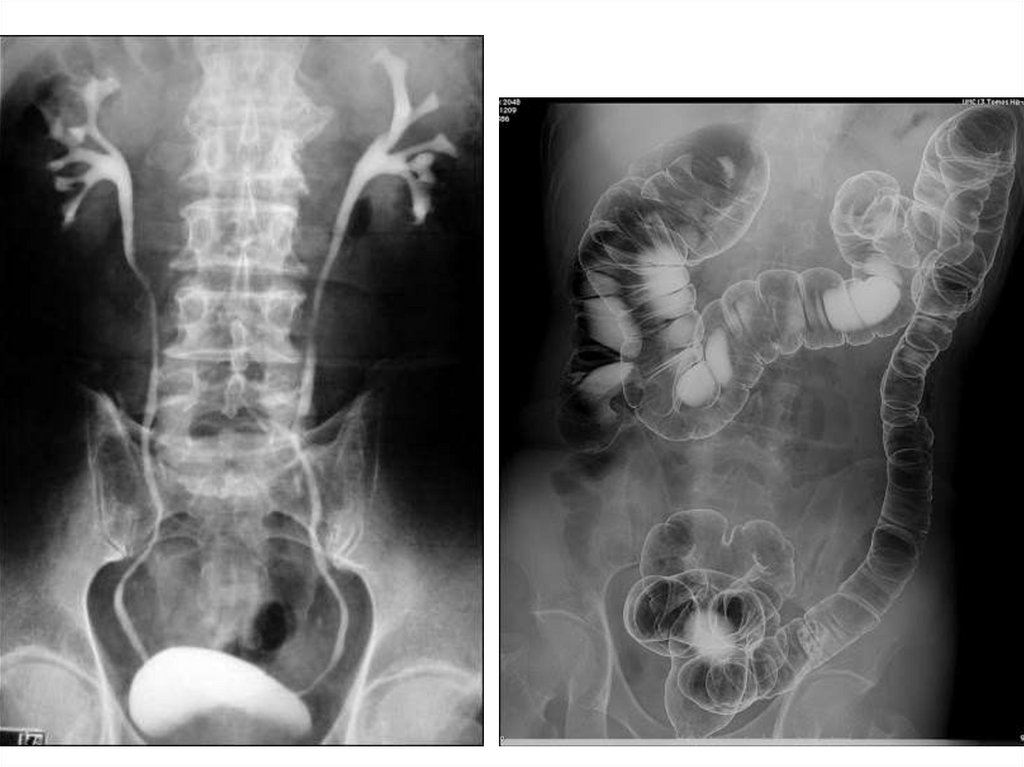

Рентгенография

Рентгеноконтрастные препараты

Рентген-контрастные вещества

Водорастворимые Водонерастворимые

Ультравист,

Омнипак

BaSO4

Газы (воздух, СО2)

Ангиография